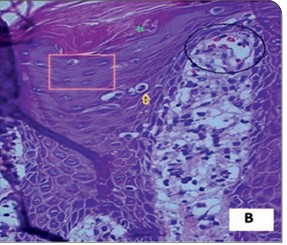

Wolf’s isotopic response refers to the occurrence of a new dermatosis at the site of a previously healed and unrelated skin condition. While commonly associated with viral triggers such as herpes simplex or zoster, non-viral initiators are rarely reported. We present two unique cases of psoriasis developing exclusively at sites of old scars from non-viral causes. The first case involved a 33-year-old male who developed a psoriatic plaque over a thermal burn scar on the dorsum of the hand. The second case featured a 28-year-old male with psoriatic lesions localized to an atrophic scar following a traumatic injury to the shin. Both cases lacked involvement of other body areas. Diagnosis was confirmed by clinical features, dermoscopy, and histopathology. These cases highlight an atypical presentation of Wolf’s isotopic phenomenon and underscore the potential role of localized immune dysregulation and scar-mediated vulnerability in the development of secondary dermatoses.